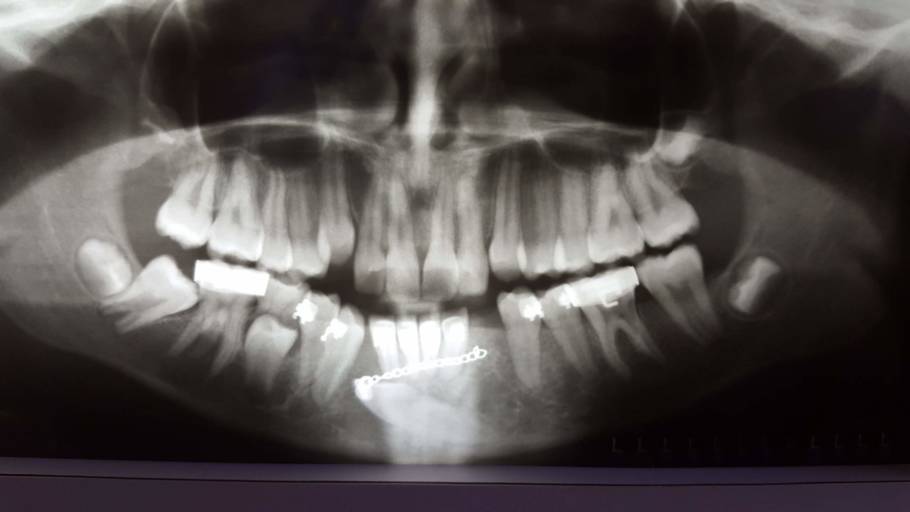

How should I fix the problem with my transmigrated mandibular canine?

I have a transmigrated mandibular canine. It is very far into my jaw. My orthodontist decided to attach a button onto the tooth, run a chain through my gums and attach it to my 2nd furthest back tooth. This constant pressure is moving the tooth into...

What can this be?

I went for a wisdom tooth removal but they found this space under tooth #24 after doing my X-ray examination.. I’m really scared that I might loose the tooth or have to have a tooth removed. I don’t have any pain with the tooth and no problems as to...